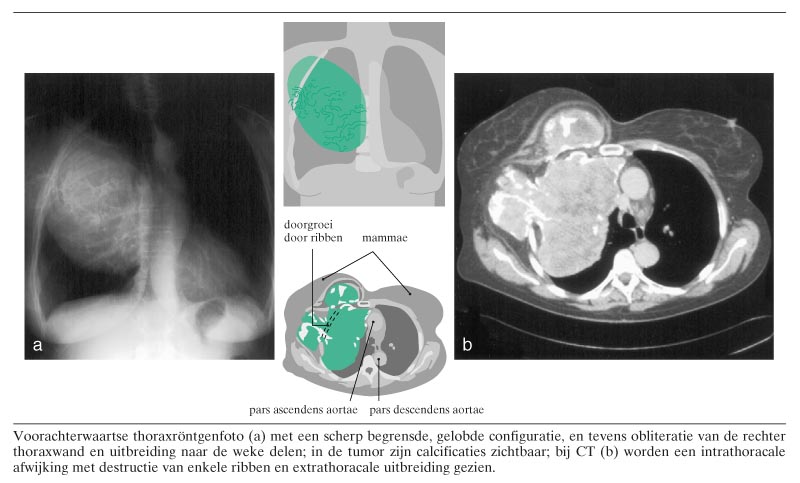

Een 55-jarige vrouw werd na een geringe verkoudheid erg dyspnoïsch, met axillaire pijn bij het hoesten. Verder voelde zij zich niet ziek. Zij vertelde al circa 30 jaar een kleine zwelling te hebben op de thoraxwand. Bij lichamelijk onderzoek werd een grote zwelling bij het rechter sleutelbeen gepalpeerd met axillaire venectasieën. Op de thoraxröntgenfoto was een scherp begrensde, gelobde configuratie zichtbaar, met obliteratie van de rechter thoraxwand, calcificaties en uitbreiding naar de weke delen (figuur). Bij CT werd een grote intrathoracale afwijking gezien, 20 cm bij 19 cm, met wisselende densiteiten, uitbreiding naar de weke delen en…